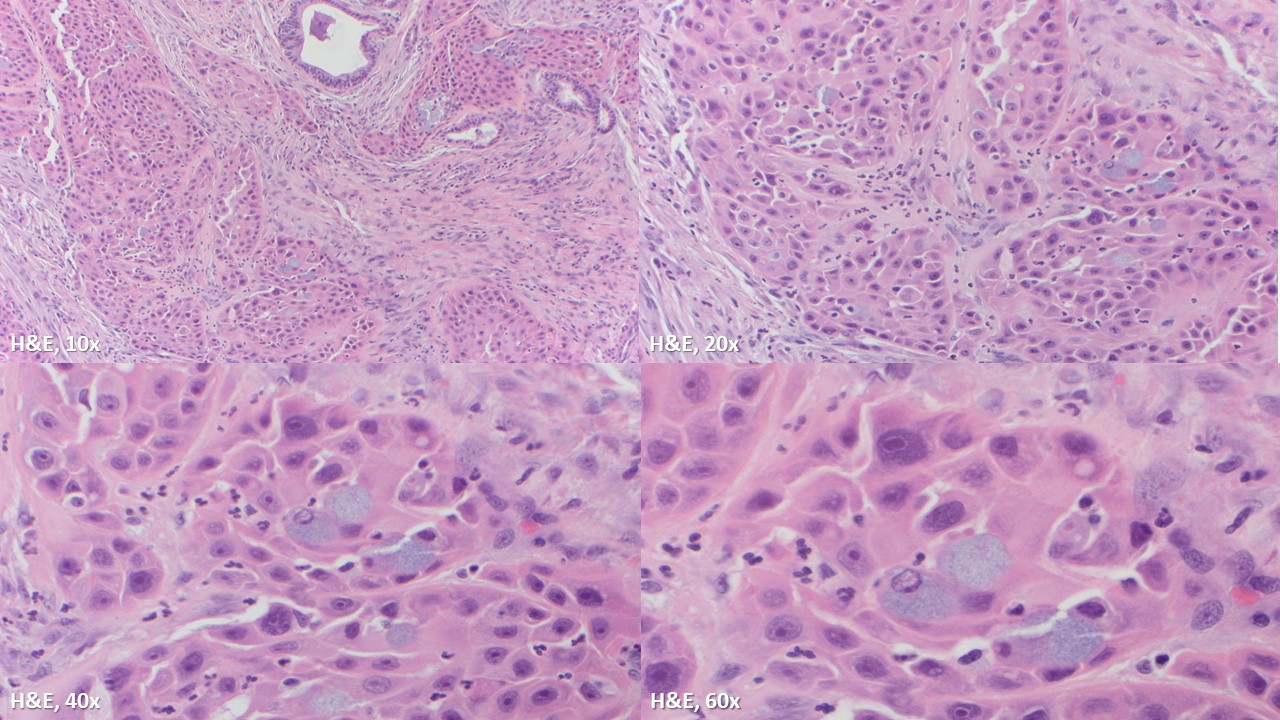

The specimen is cellular and consists of clusters and sheets of large atypical cells with macronucleoli and moderate amounts of somewhat dense cytoplasm. Occasional cells appear to have intracellular mucin and represent muciphages. Scattered benign ductal cells and acini are noted. Necrosis is absent. These findings are consistent with a high-grade salivary gland neoplasm, and a high-grade mucoepidermoid carcinoma is favored on cytology. Subsequent resection confirmed the cytomorphologic impression and showed also perineural invasion.

Mucoepidermoid carcinoma is the most common salivary gland malignancy in children and adults, and the most common malignancy of major and minor salivary glands. Low-grade tumors are more commonly cystic, while high-grade tumors are solid and infiltrative. The diagnostic feature is the combination of mucous cells, epidermoid/squamoid cells, and intermediate cells (which resemble squamous metaplastic cells). High-grade mucoepidermoid carcinomas have a greater proportion of squamoid cells with more cytologic atypia.